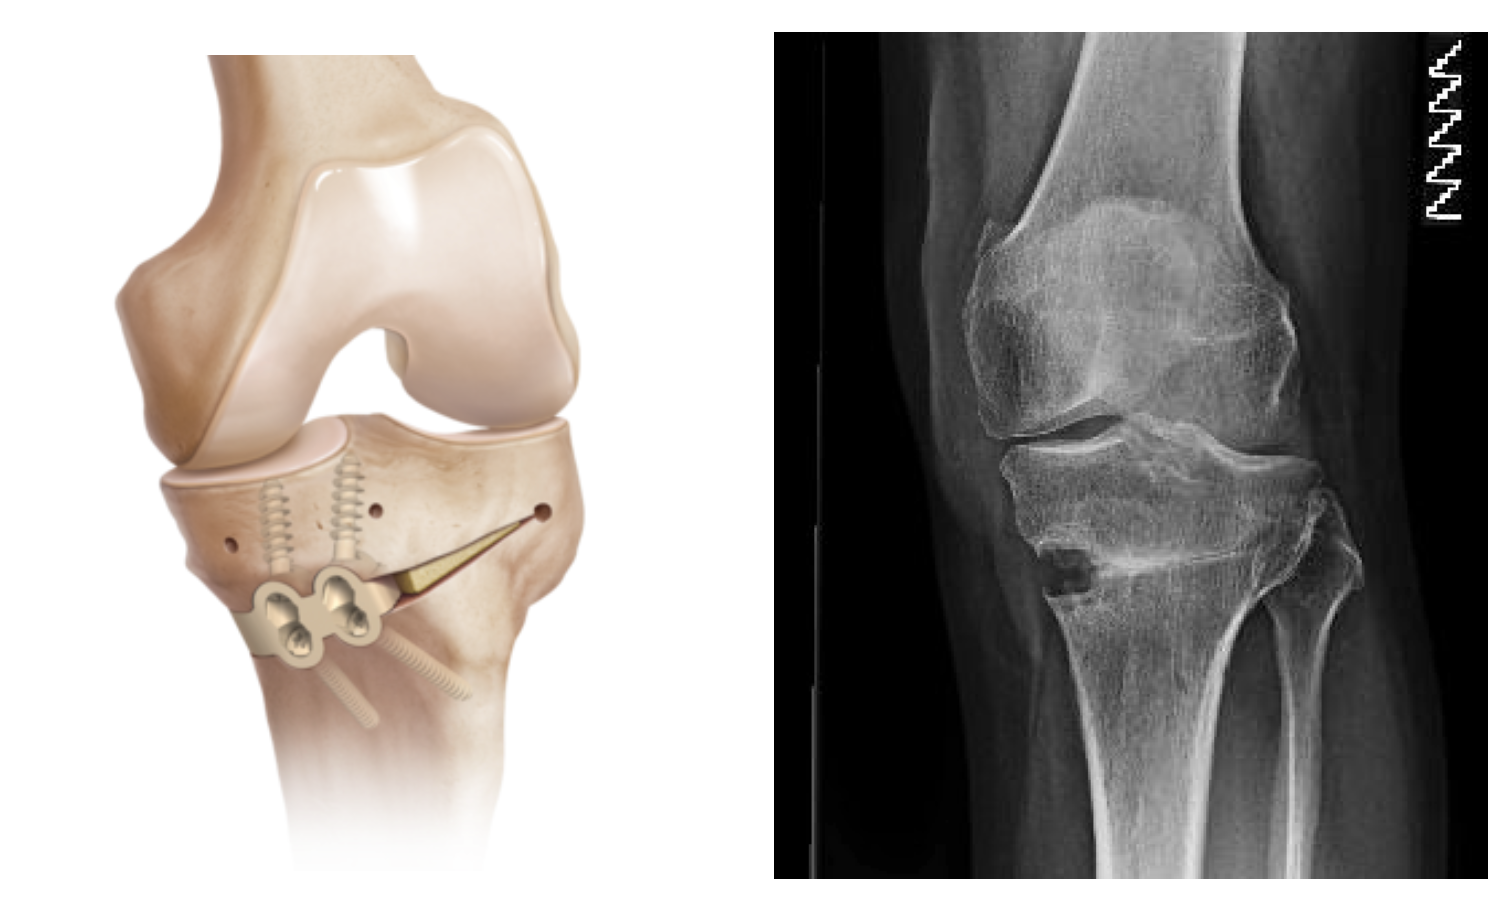

HIGH TIBIAL OSTEOTOMY

I am now more active than I have been in many years

I had High Tibial Osteotomy surgery with Mr Mihai Vioreanu in November 2016. Having osteoarthritis in my left knee left me unable to enjoy a normal active life without pain if I spent long periods walking or standing.

"Enjoying an active life"

I had High Tibial Osteotomy surgery with Mr Mihai Vioreanu in February 2015. I had been in terrible pain with my knee in 2014 following arthroscopic 'clean-out' performed in a different hospital. Mr Vioreanu was excellent during all my consultations with him. He spoke openly and plainly about the surgical procedure in layman's terms. He thoroughly discussed all the pros and cons involved. Mihai was always ready and available to assist me after surgery. I am now back to a normal lifestyle and en

"Best decision I made"

I decided to go for it and can honestly say it was one of the best decisions I made. 6 months later and I'm walking and hiking pain free, performing all manner of exercise and am working towards running/jogging.

BILATERAL HIGH TIBIAL OSTEOTOMY

"Mihai professionalism and experience is top class"

Mihai put a plan in place over three years to carry out surgery on both legs. The surgeries were a great success.